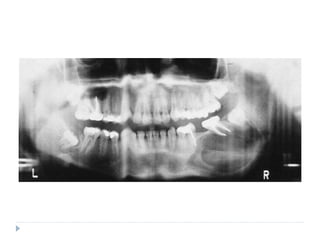

RADIOGRAPHIC FEATURES

 Radiolucent destruction of the bone with ragged and

ill-defined margins

 Radiolucency may begin as several small areas

which eventually enlarge and coalesce

 Patchy loss of the lamina dura is one of the early

sign of Burkitt’s lymphoma